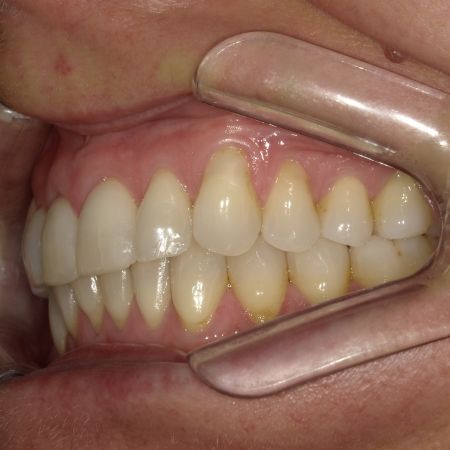

Vor der Behandlung